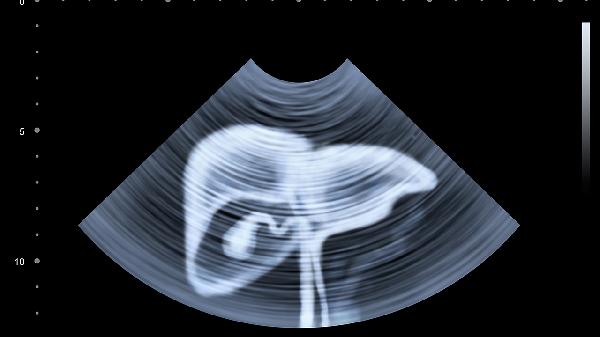

胆囊泥沙样结石的典型超声影像可见胆囊底部或体部出现均匀或不均匀的细点状高回声,颗粒直径通常小于3毫米,呈沙粒样分布。当患者改变体位时,这些高回声颗粒可随胆汁流动形成"暴风雪"样动态表现。部分病例可见胆囊壁增厚或胆汁分层现象,上层为无回声胆汁,下层为高回声沉积物。部分沉积物可能因胆固醇结晶析出而出现"彗星尾"征,即细小强回声后方伴多重反射伪影。

非典型表现包括沉积物呈现片状高回声区但无声影,需与胆囊息肉或肿瘤鉴别。少数情况下,沉积物过于稀薄可能导致回声强度减弱,易被误判为胆汁淤积。合并急性胆囊炎时,超声还可显示胆囊壁三层结构消失、周围积液等继发征象。值得注意的是,部分胆固醇结晶沉积可能呈现类似泥沙样结石的超声特征,但结晶体积更小且分布更均匀。